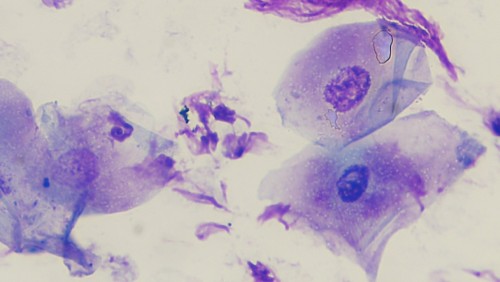

Aucun élément figuré n’est observé aux raclages cutanés ni aux curettages auriculaires. La cytologie cutanée montre la présence de rares polynucléaires neutrophiles dégénérés et de rares bactéries de type cocci en position intracellulaires (phagocytose), de très nombreux cornéocytes parakératotiques (cf. photo 4). Aucun kératinocytes acantholytique n’est observé. La cytologie auriculaire montre de très nombreuses bactéries de type cocci et des polynucléaires neutrophiles en quantité modérée sans images de phagocytose. La culture fongique est négative.